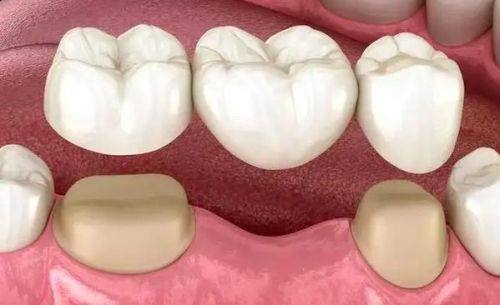

2. 口腔种植:诊所医生团队经验多,在种植牙齿方面技术成熟,为患者提供可靠的种植服务。

7. 全瓷牙冠:2000 - 5000元

17. 烤瓷牙:800 - 2000元